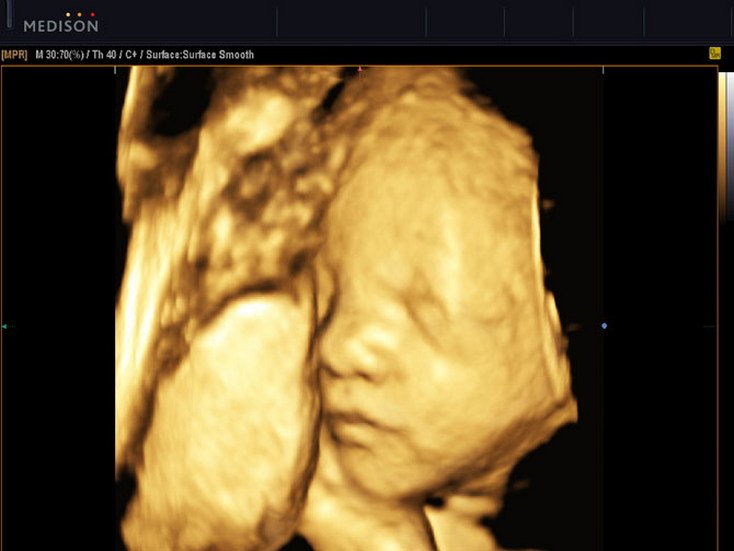

4D Foetal Face

4D Sonography -Foetal Face